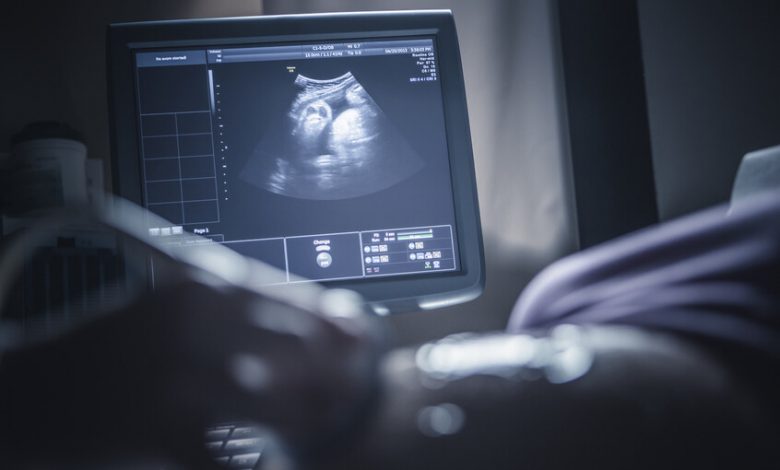

حذر باحثون من أن تعرض الجنين داخل الرحم حتى لمستويات منخفضة من مادة كيميائية شائعة، يمكن أن يتسبب في اضطراب النمو الطبيعي، مع ظهور تأثيرات تؤدي إلى “تأنيث الذكور وتذكير” الإناث”.

وأشار الباحثون إلى أن تعرض الجنين داخل الرحم حتى لمستويات منخفضة من مادة ثنائي الفينول أ (BPA) الصناعية، قد يؤدي إلى اضطرابات دائمة في النمو الجنيني، مع آثار طويلة المدى على الصحة.

وأظهرت دراسة سويدية حديثة من جامعة أوبسالا أن هذه المادة، التي تُستخدم على نطاق واسع لتحسين متانة البلاستيك ومقاومته للحرارة، تحاكي عمل الهرمونات الطبيعية في الجسم عند تسربها من العبوات إلى الطعام والشراب. وأكد الباحثون أن التعرض حتى للجرعات التي كانت تُعتبر آمنة سابقا يمكن أن يسبب عواقب صحية عميقة.